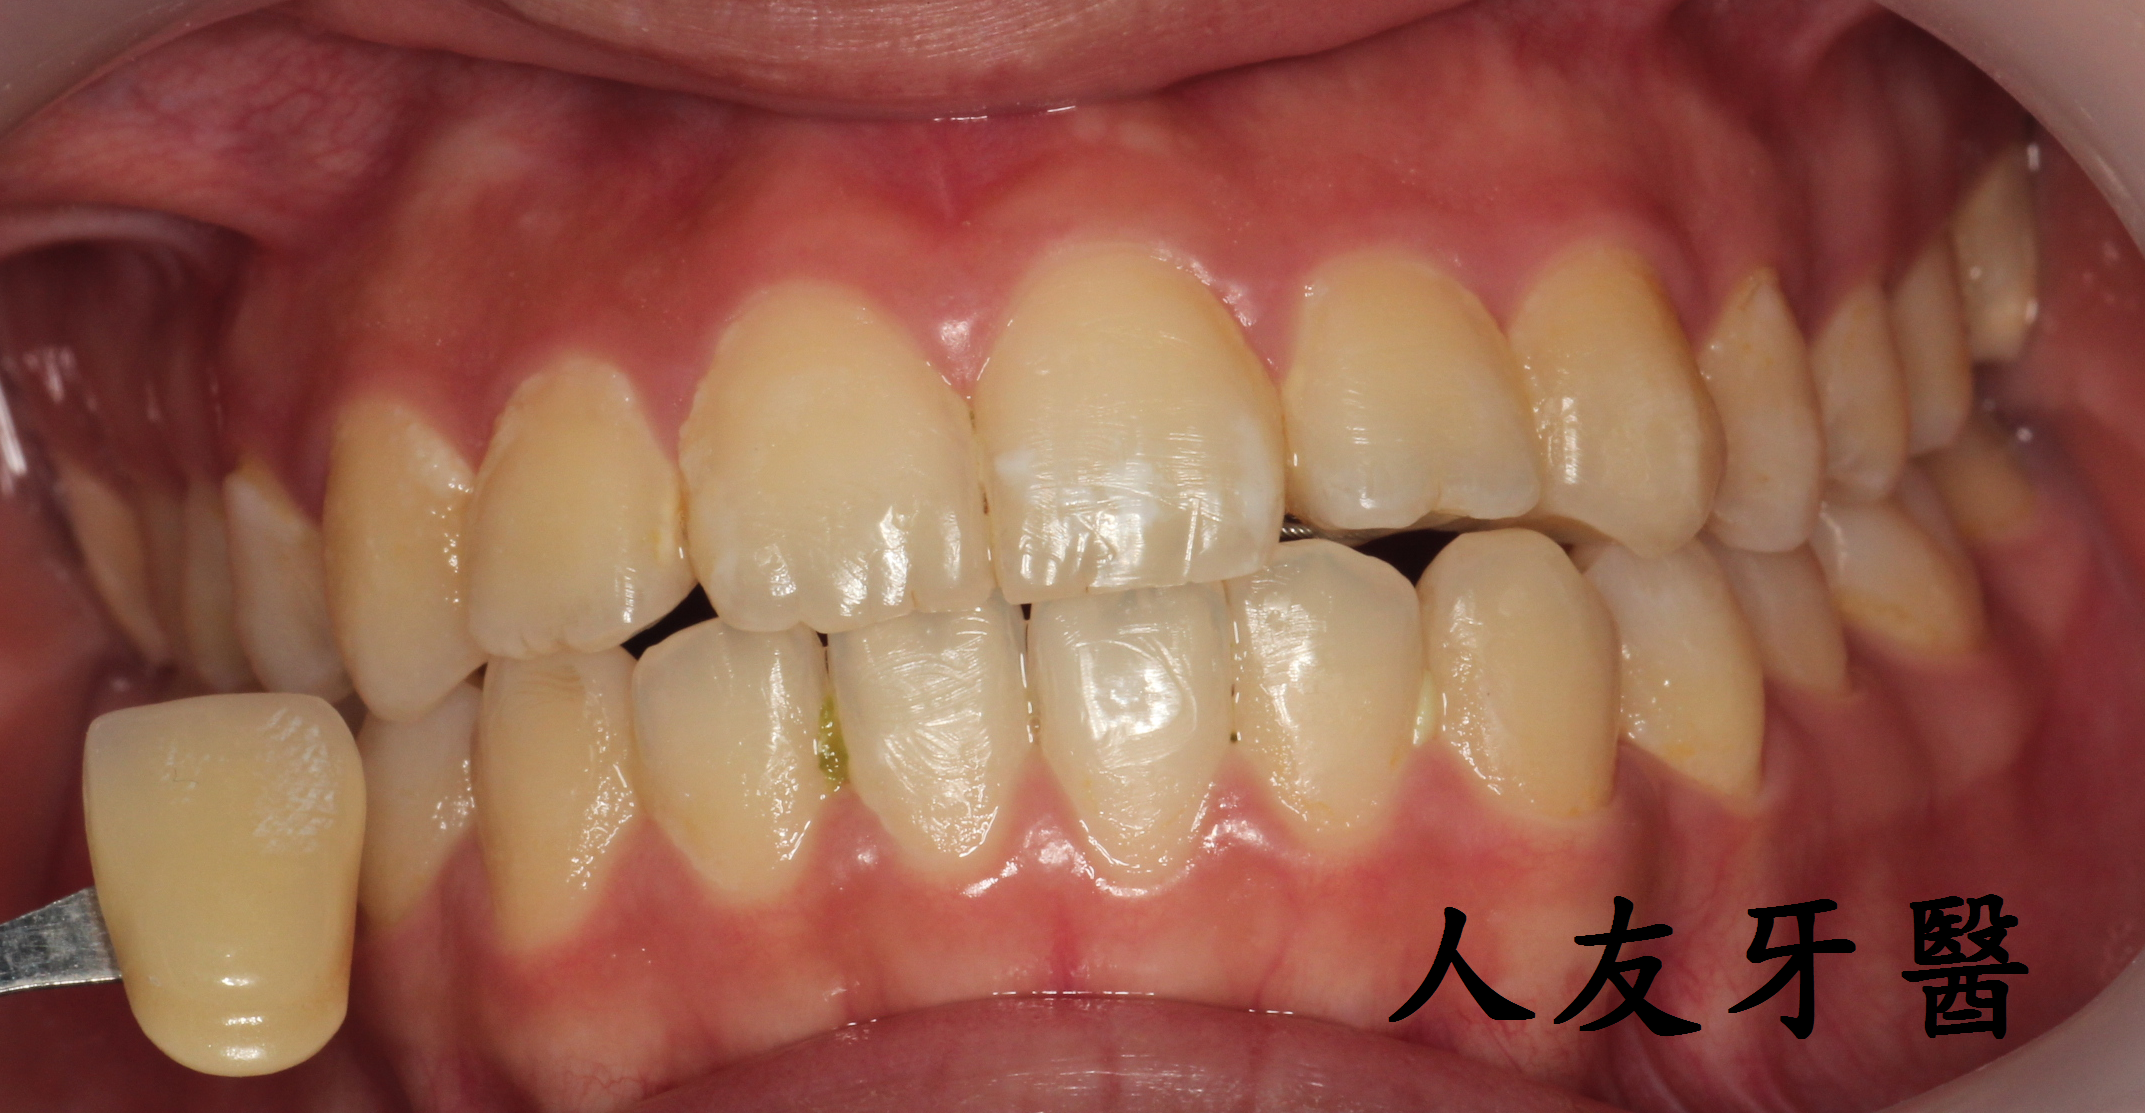

案例分享

有一位26歲女患者訴說她以前洗牙很容易敏感、會痠,但經過本診所進行的舒適型噴粉淨白方式,反而讓她驚訝為什麼不會痛、不會痠,甚至可以改善長期下來愛喝茶、咖啡導致的深層茶垢,這是因為我們使用相較於傳統清潔方式不同地方所在。

左為治療前 右為治療後